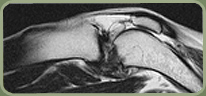

Canine with cruciate tear.

This mix breed presented with abulatory deficite and the MRI performed clearly demonstrated a Cruciate Ligament Tear in the Knee, seen in this sagittal T2 image .